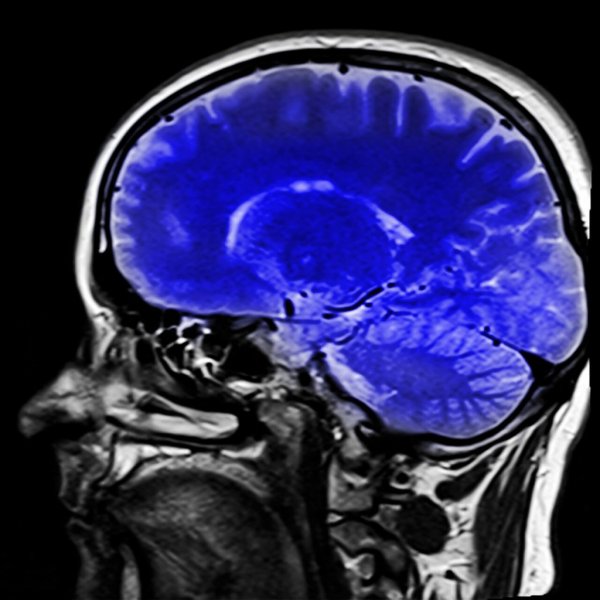

Istnieją testy neurologiczne, które pomagają lekarzom zdiagnozować ten zespół. MRI może pokazać, jaki rodzaj udaru wystąpił, a to pomoże im określić, z czym mają do czynienia.